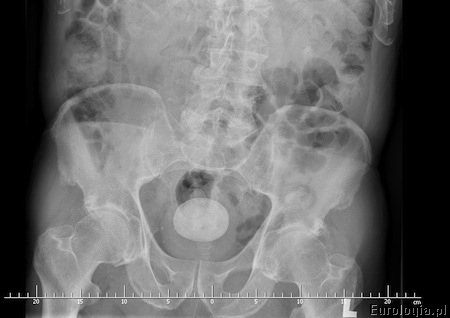

Fot. Zdjęcie rentgenowskie z widocznym złogiem w pęcherzu moczowym